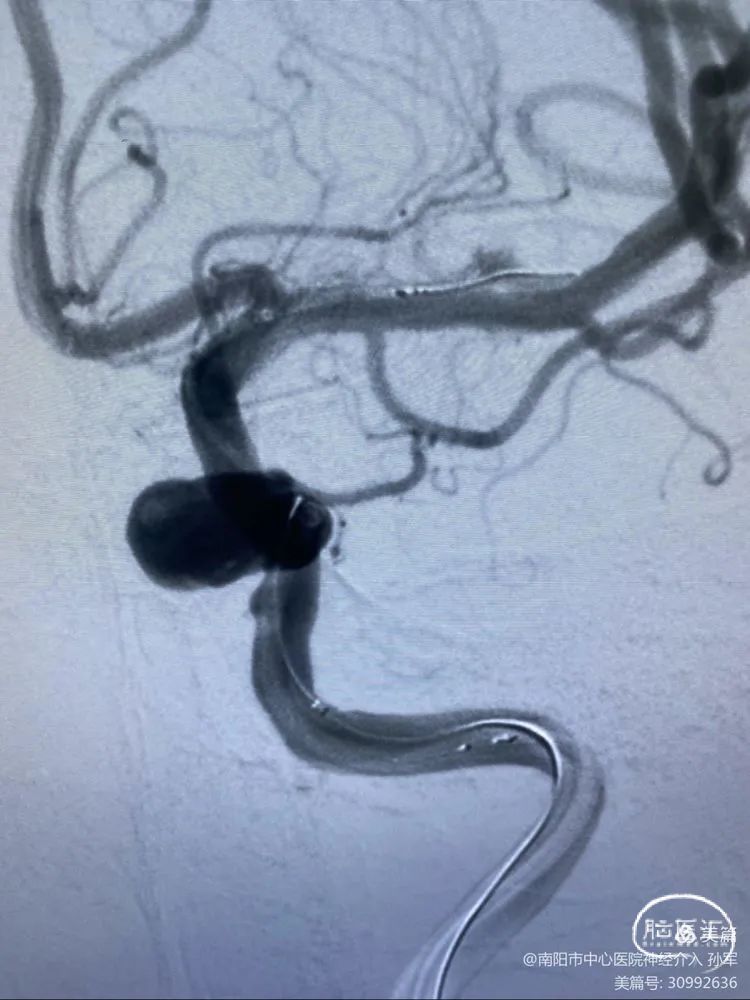

患者:女性,54岁

诊断:虹吸段大动脉瘤,瘤颈部分瘤化

术前影像学资料

1

7F长鞘内置5F Navien ➕ marksman ➕ Echelon10。

2

到目前一切都顺利。

3

随着支架的释放,支架远端导丝移动到大脑中动脉分支。

4

经过调整,支架远端导丝竟然刺向豆纹动脉,且难以摆脱,考虑到支架释放后支架导丝还要前行很远,一旦刺破豆纹动脉将会导致灾难性后果。

5

遂回收支架,重上marksman至M2远端。

再次释放支架,打开良好,支架头端导丝位置良好。